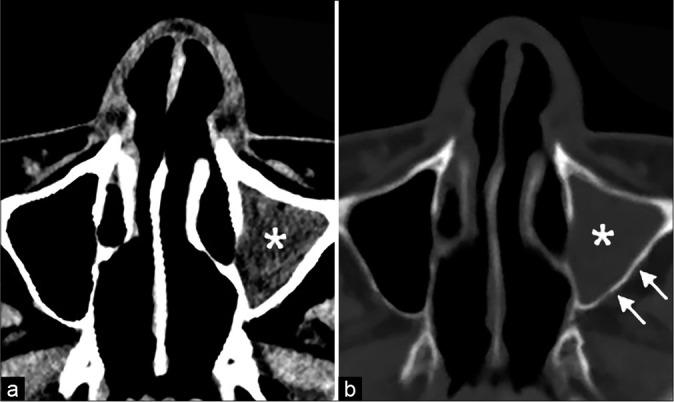

An 18-year-old male was admitted to the hospital with headache, nausea, and vomiting for 2 days. The patient denied a history of head trauma, operation, and any other infectious and systemic diseases, and he was not taking any medication. CT scan demonstrated a mixed density lenticular mass with some air collection in the frontal region. The axial sinus CT image demonstrated opacification of the left frontal, ethmoid, and maxillary sinuses. An emergency operation confirmed the diagnosis of frontal SEDH associated with EDA and frontal osteomyelitis. The frontal EDH, abscess, and the infected bone were completely removed during the operation without opening the dura. The patient recovered well after receiving 8 weeks of antibiotic therapy, and a cranioplasty was performed 9 months after the craniectomy.

一名18岁男性因头痛、恶心和呕吐2天入院。患者否认有头部外伤、手术史以及任何其他感染性和全身性疾病史,且未服用任何药物。CT扫描显示额叶有一混合密度的透镜状肿块,内有气体积聚。轴位鼻窦CT图像显示左侧额窦、筛窦和上颌窦混浊。急诊手术证实诊断为额叶SEDH合并EDA及额叶骨髓炎。手术中在未打开硬脑膜的情况下将额叶EDH、脓肿及感染骨完全清除。患者接受8周抗生素治疗后恢复良好,颅骨切除术后9个月进行了颅骨成形术。